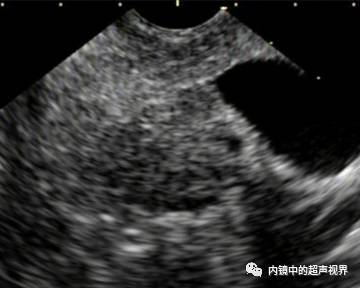

我现在使用的超声内镜DR可调节范围为30-90。以下三张图片显示的是同一个胰头肿物,肿物回声与胰腺回声非常接近,DR分别为90、70、40,其它参数相同,您更喜欢哪一张。

胰头占位